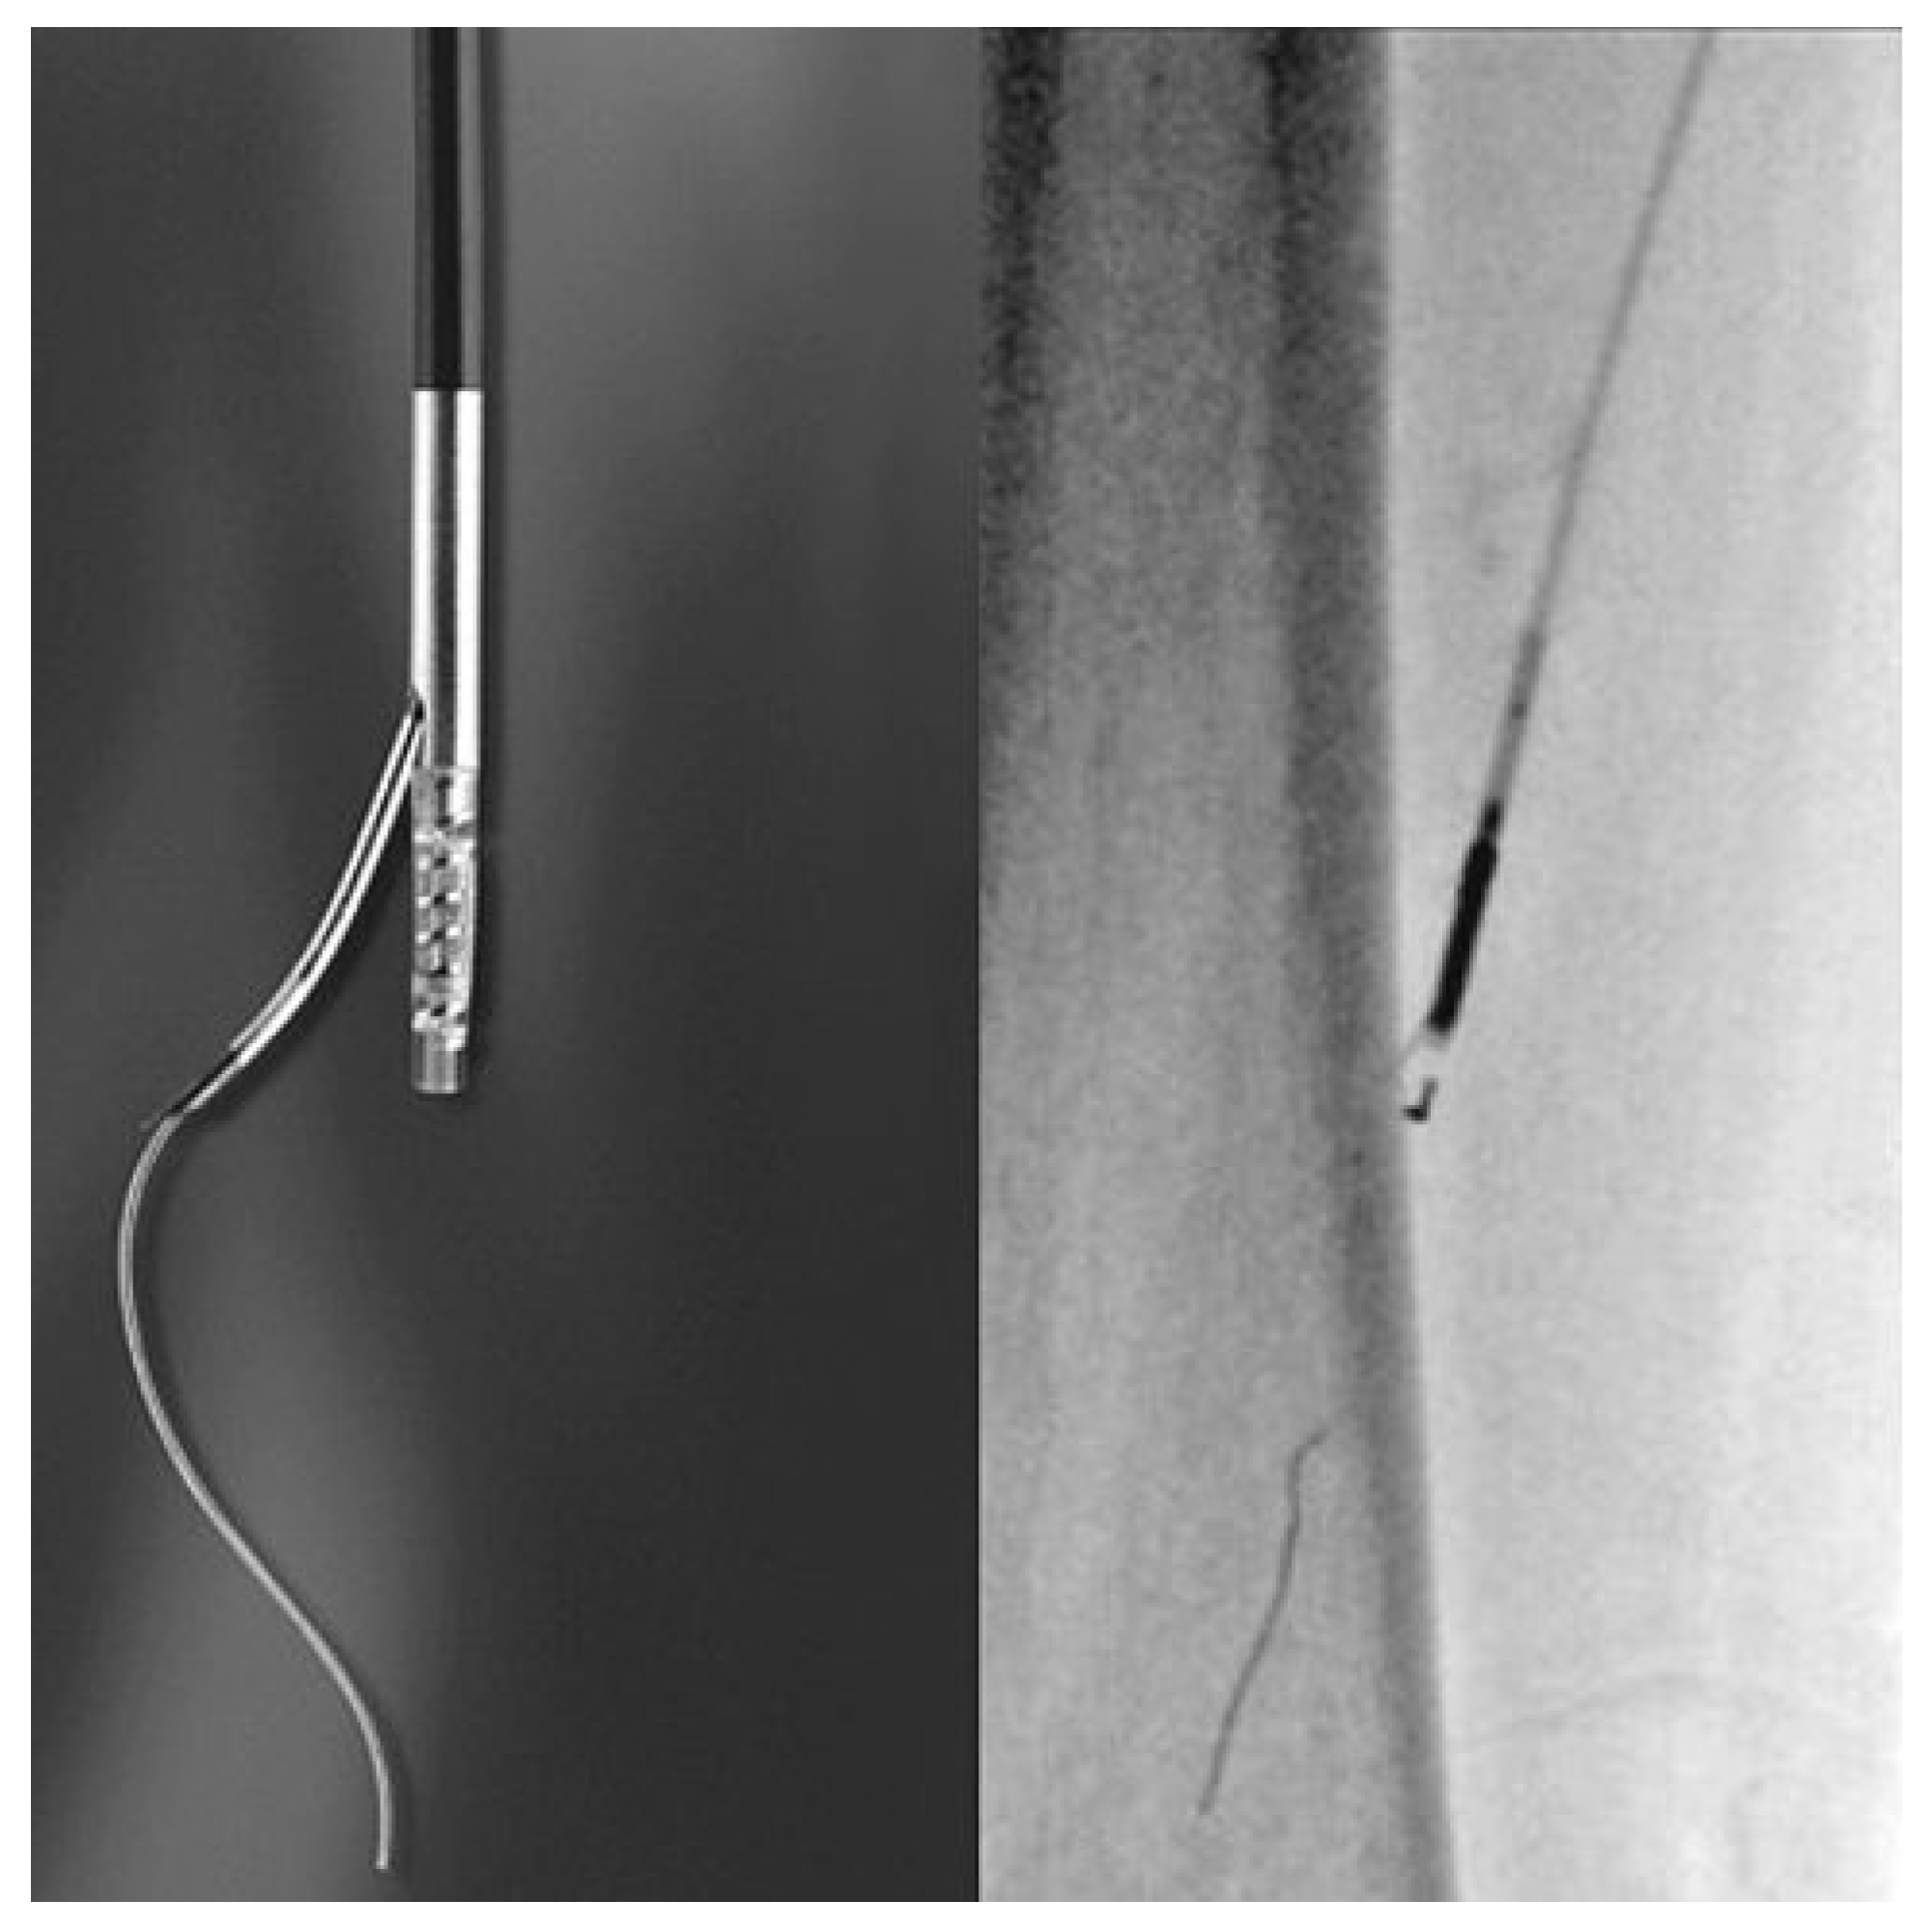

Le rationnel pour utiliser des «debulking devices», surtout au niveau de l’AFS, est de pouvoir éliminer le plus possible la plaque d’athérome, donc de gagner de la lumière dans des vaisseaux souvent très infiltrés par l’athérosclérose et aussi d’éviter les désavantages liés au baro-trauma du vaisseau lors de l’inflation du ballonnet. Il existe plusieurs modes pour effectuer l’athérectomie: l’athérectomie directionnelle en utilisant le Silverhawk™ device (ev3, Paris, France, Figure 3), l’athérectomie rotationnelle avec aspiration avec le Pathway PV Atherectomy system™ (Pathway medical, Redmond, WA, Etats-Unis), l’athérectomie rotationnelle à haute vitesse avec le Rotablator system™ (Boston Scientific, Natick, MA, Etats-Unis) et l’athérectomie orbital avec le Diamondback 360° Orbital Atherectomy device (Cardiovascular system, St-Paul, MN, Etats-Unis).

Figure 3. Silverhawk Atherectomy System™ (ev3, Paris, France).